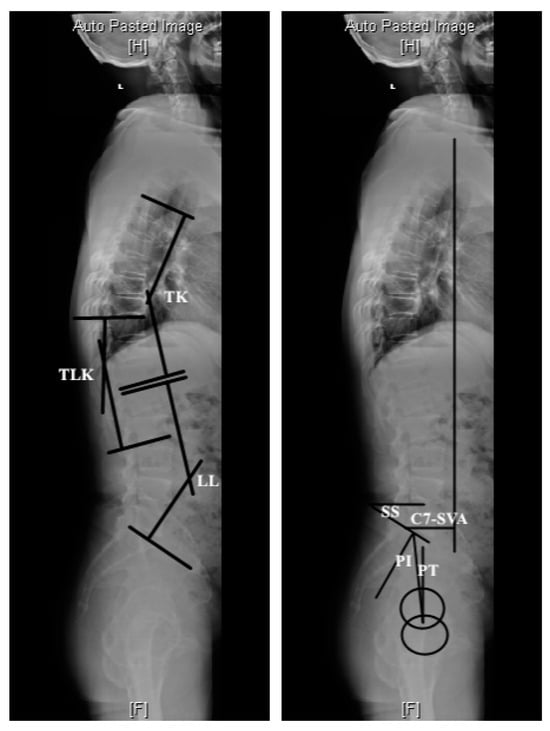

4.1. Normal Sagittal Alignment

4.2. Thoracolumbar Junctional Kyphosis

4.4. Compensatory Mechanisms for Sagittal Balance